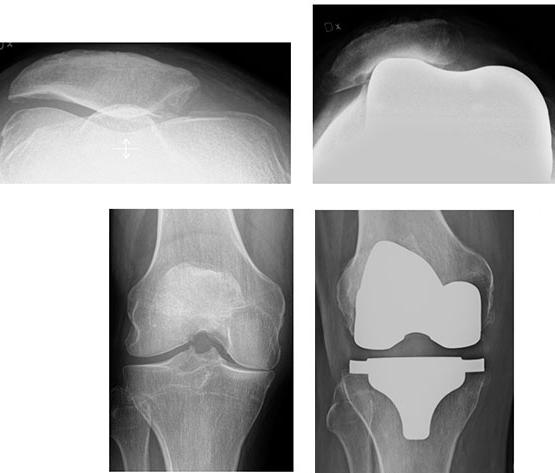

Offentlig upphandling av höft- och knäprotesimplantat

Personliga erfarenheter och reflektioner kring en nyligen genomgången upphandling.

Maziar Mohaddes, Ann-Charlotte Westerlund, Johan Kärrholm

En regnig tisdagmorgon, mellan två operationer, frågade sektionschefen om jag ville delta som representant för läkargruppen i offentliga upphandlingar för höftoch knäledsimplantat och tillhörande bencement. Överläkarkollegan som förtjänstfullt hade skött detta tidigare hade gått i pension och nu behövdes en ersättare! Min vana trogen svarade jag: ”absolut, det låter spännande”.

Efter tre dagar kom det kallelser till inte mindre än åtta heldagsmöten under april-juni! Jag kontaktade chefen som också höjde ögonbrynen. Hen bad mig undersöka saken och det visade sig att upphandlingsavdelningen ville se ett ökat engagemang hos professionen vid upprättande av kravspecifikationer.

Under två av de bokade dagarna skulle det vara öppet-hus där företagen hade möjlighet att visa upp sina nya produkter och svara på eventuella funderingar. Det framkom också att två dagar hade reserverats utöver det beräknade behovet på totalt sex. Detta var en optimistisk kalkyl för det kom att behövas ytterligare fyra möten under hösten.

Ökat professionellt engagemang i arbetet med offentliga upphandlingar är

SUMMERING

Summerar man så kan det finnas både vinster och risker då vi debatterar vidare kring ett nationellt ramavtal. Onekligen finns det ett intresse för att förenkla upphandlingsförfarandet för implantat. Detta märks tydligast då kollegor som har varit delaktiga i upphandlingar tillfrågas om deras erfarenhet. Vidare förefaller det finnas ett intresse hos representanter i Swedish Medtech att frågan diskuteras. Styrelsen för Svenska höft- och knäföreningen tog upp frågan vid senaste styrelsemötet och valde att ställa sig positivt till tanken om att utvärdera möjligheterna för upprättandet av ett nationellt ramavtal. Ett beslut om frågan ska drivas vidare av Svenska höft- och knäföreningen kommer att tas vid styrelsemötet som följer ortopediveckan 2019. I väntan på det vore synpunkter och tankar från enskilda kollegor och även andra berörda inom sjukvården som till exempel operationssköterskor, representanter för upphandlingsavdelningar, materialkonsulenter samt företagsrepresentanter högst värdefulla.

viktigt, vilket speglades av att projektgruppen representerade hela regionen. Jag anser att detta arbete har varit oerhört lärorikt även om vissa frågetecken kvarstår, särskilt beträffande kostnadseffektiviteten i upphandlingsprocessen.

Min bakgrund som registermedarbetare och författare till delar av höftprotesregistrets årsrapport bidrar nog också till känslan att orimligt mycket arbetstid används vid offentliga upphandlingar av höft- och knäprotesimplantat. I Sverige används till exempel en mycket snäv selektion av implantat vid majoriteten av höftprotesoperationer.

Under de senaste två åren och i cirka 80% av fallen har man valt bland sju olika cup-design och tre stam-design. Samma typ av upphandlingar förekommer runt om i landet där kollegor är mer eller mindre delaktiga. Rimligen borde processen med offentliga upphandlingar kunna strömlinjeformas på ett bättre sätt. Man skulle inte behöva uppfinna hjulet gång på gång!

Sveriges proteskirurger skulle kunna enas om att ha ett nationellt ramavtal. I detta avtal skulle implantaten där den löpande dokumentationen uppfyller standardiserade krav, överenskomna av professionsrepresentanter, kunna upphandlas.

Nya eller modifierade implantat skulle kunna särbehandlas. Här bör det krävas att implantatet utvärderas i vetenskapliga studier och genomgår annan strukturerad uppföljning på ett begränsat antal kliniker. Lämplig typ av monitorering beslutas av professionen mot bakgrund av internationella erfarenheter och andra tillgängliga data, inte minst från kvalitetsregister i den mån sådana data finns. Den grupp av intresserade proteskirurger som tar ställning till enskilda implantats befintliga dokumentation skulle kunna tillsättas av Höft & Knäföreningen.

Det finns säkert flera knutar att lösa upp innan man kan sjösätta ett nationellt ramavtal. En viktig fråga är om vi inom professionen är intresserade av ett nationellt ramavtal för upphandling av i första hand primära höft- och knäproteser. Det kan vara svårt att omedelbart inse föroch nackdelar.

Potentiella fördelar är framför allt en enklare process och ett lägre pris. Frågan är vilka nackdelar som finns. Dessa frågor är inte helt lätta att bena ut, men en debatt mellan berörda parter inom sjukvård, leverantörer/tillverkare och kanske också sjukvårdsadministratörer och huvudmän i OM, eller på något av våra kommande möten, skulle kunna bidra till klarhet.

Som underlag för denna debatt har vi med hjälp av representanter för operationssköterskor på Sahlgrenska valt att presentera en lista med för- och nackdelar vid upprättandet av ett nationellt ramavtal.